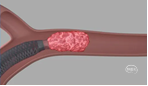

手术过程:右侧股动脉置入8F 股动脉鞘,主动脉弓及超选造影提示右侧颈内动脉闭塞-栓塞性病变(大负荷量栓塞)。

泥鳅导丝携带125cm多功能导管导引088抽吸导管8F 115cm置于颈总动脉,在泥鳅导丝导引下可单独上至海绵窦段。下图1、2

远端通路导管6F 130cm导引心玮吞川抽吸导管到达血栓近端进行第一次抽吸后海绵窦后膝显影,远端仍闭塞,血管迂曲严重。下图3

微导丝、微导管导引6F 130cm远端通路导管越过海绵窦后膝,并导引心玮吞川抽吸导管深入残余血栓进行第二次抽吸,眼动脉显影,眼段以远仍闭塞。

远端通路导管6F 130cm在微导丝及微导管导引下越过虹吸弯,并导引088抽吸导管到达血栓近端,应用其大口径及强负压对血栓进行第三次抽吸,直接原位抽出血栓,血管完全再通,无血栓逃逸及残留。